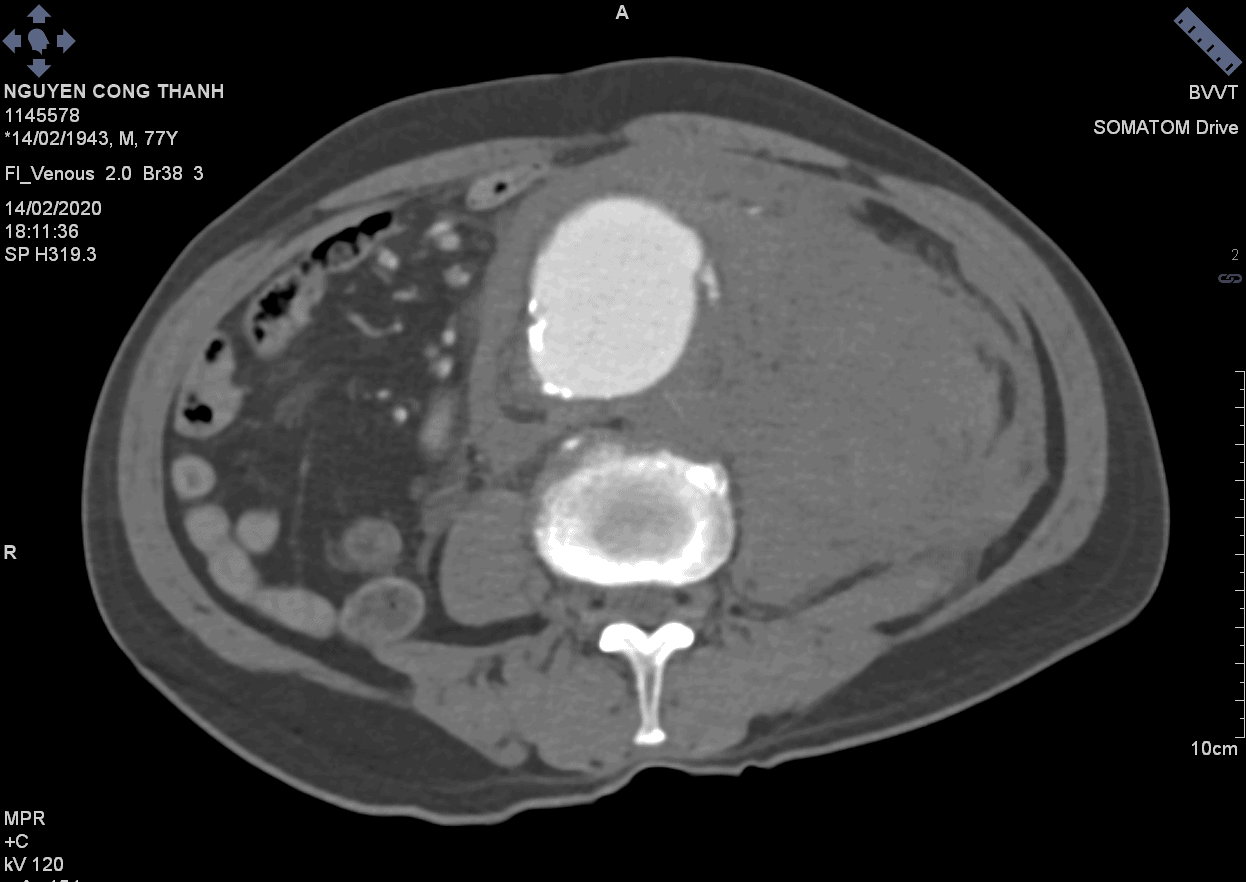

Vỡ phình ĐM chủ bụng

Vỡ phình ĐM chủ bụng - Ảnh 4

» Thông tin: Nam giới – 77 tuổi.

» Lâm sàng: Đau bụng cấp.